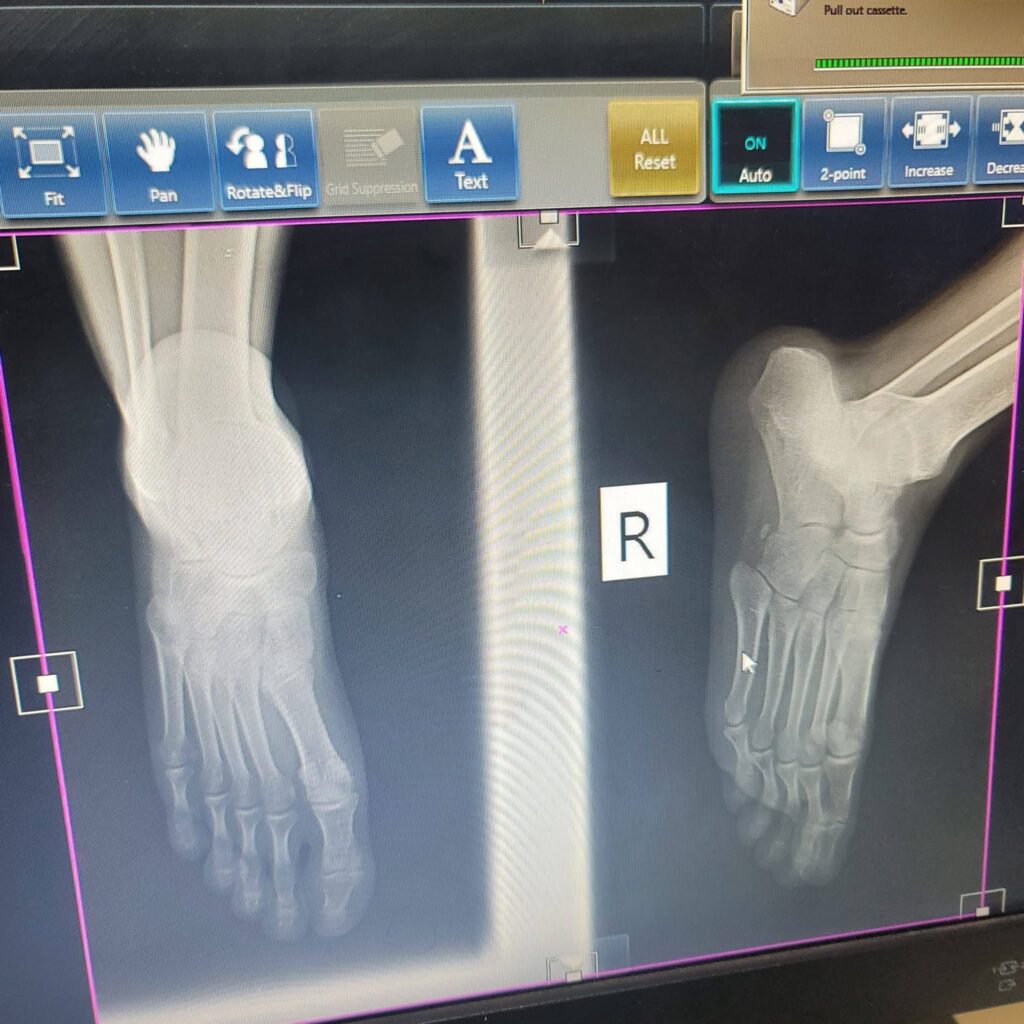

However, X-ray results later confirmed that Ian had sustained a serious tarsal injury.